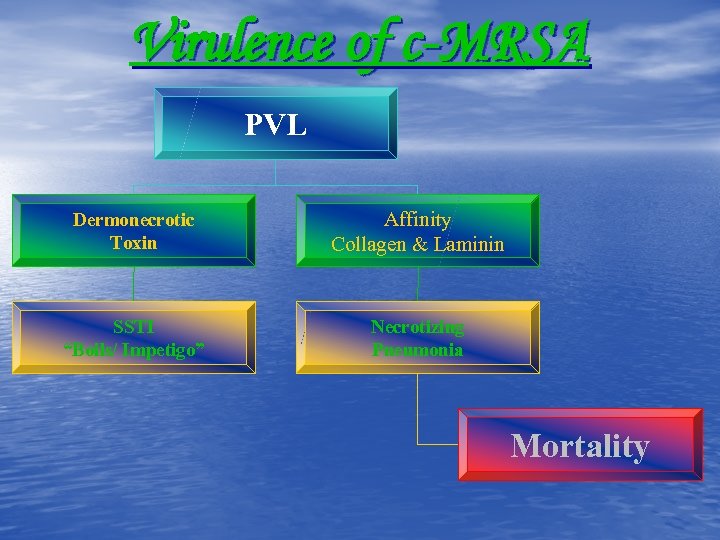

Virulence of c-MRSA PVL Dermonecrotic Toxin Affinity Collagen & Laminin SSTI “Boils/ Impetigo” Necrotizing Pneumonia Mortality

Virulence of c-MRSA PVL Dermonecrotic Toxin Affinity Collagen & Laminin SSTI “Boils/ Impetigo” Necrotizing Pneumonia Mortality